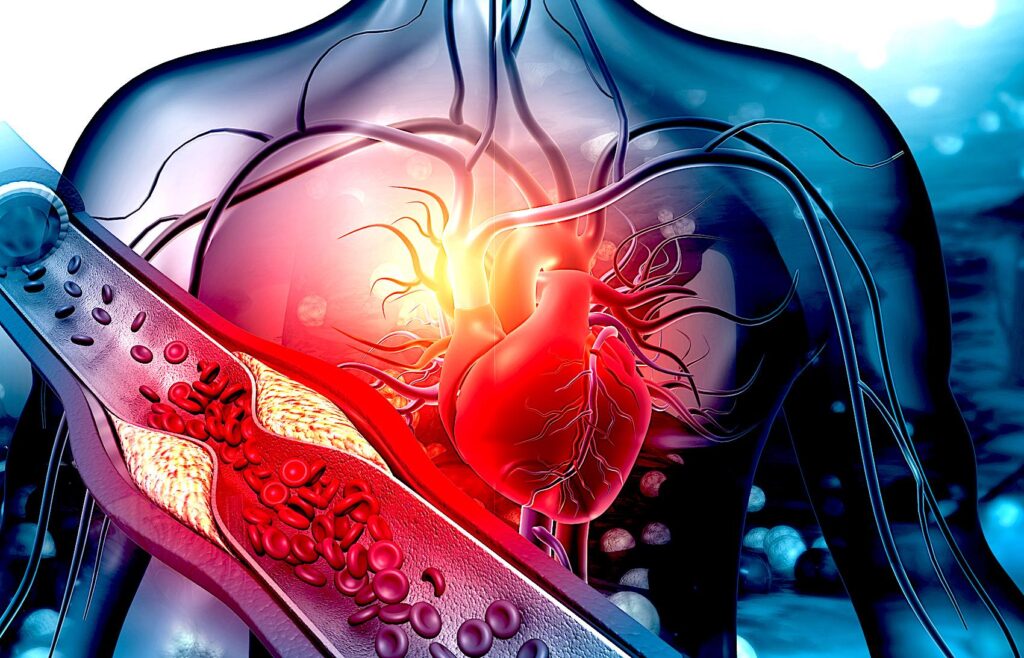

Preventie Hipercolesterolemie Ateroscleroza

Hipercolesterolemia este cantitatea in exces a grasimilor daunatoare in sangele uman. Colesterolul este o notiune abstracta intrucat nu exista o substanta cu acest nume ci o suma de substanțe grase care impreuna formeaza colesterolul și anume: HDL, Lipoproteine cu densitate mare, LDL, Lipoproteine cu densitate mica, și TG, Trigliceride. Toate aceste trei substante impreuna se constituie intr-o grupa de grasimi numita colesterol total. Lipidele sau mai exact spus lipoproteinele din componenta colesterolului se constituie in placi rigide care se depun in timp pe artere acestea pierzându-si elasticitatea. Placile rigide de aterom se pot desprinde sau rupe in situații speciale cum ar fi Hipternsiunea Arteriala care forțează vasul, efortul fizic etc. si intra in circulatia sanguina. Ele se pot opri in vasele creierului pe care le blocheaza sau in miocard (inima), dand nastere Accidentelor Vasculare Cerebrale sau Infarctului Miocardic. Hipercolesterolemia este genetica dar si alimentara. Ea poate fi diagnosticata si controlata medicamentos si alimentar.